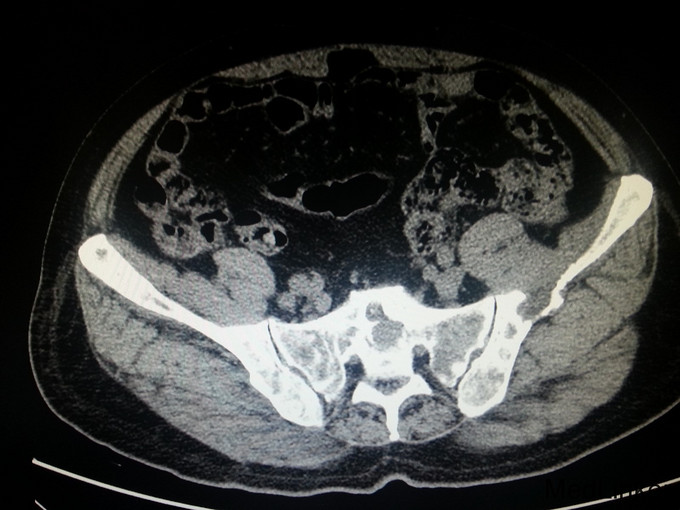

患者,男,68岁,因门诊CT检查发现前列腺肿瘤、骨转移入院

前列腺穿刺病理 :前列腺癌 Gleason4+4 PSA>100ng/ml fPSA>30ng/ml

患者入院后经会阴前列腺穿刺活检,病理诊断为前列腺癌 Gleason4+4 ;予以口服氟他胺以及静脉注射唑来膦酸、戈舍瑞林缓释剂皮下注射治疗; 治疗半年后复查 CT提示前列腺肿瘤缩小;PSA45ng/ml;患者一般情况明显好转